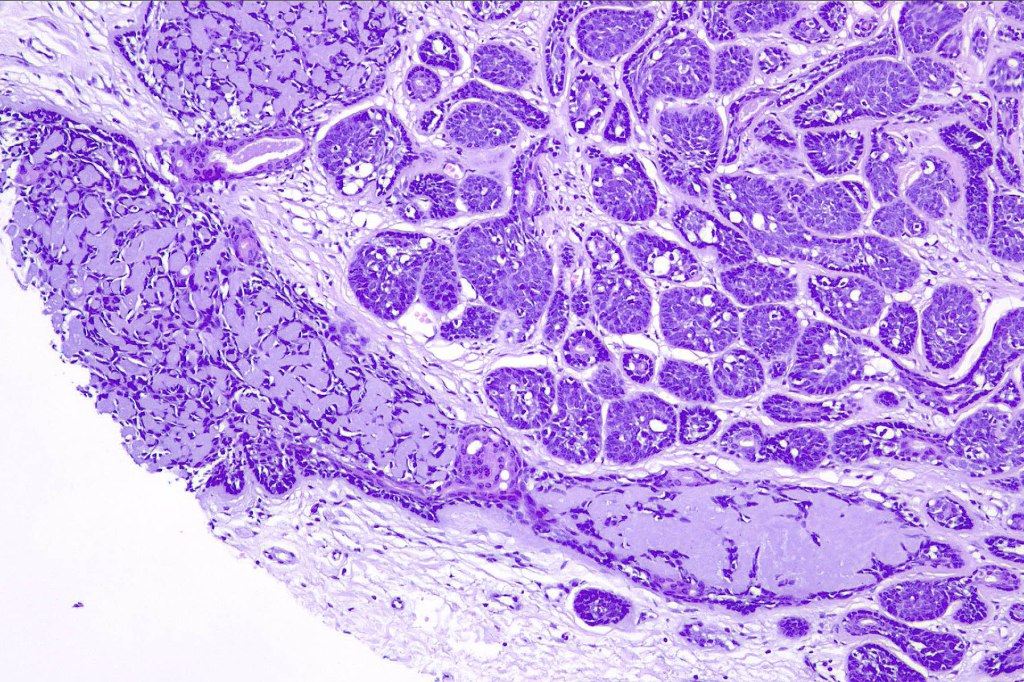

Histological features

•Dermal based

•Jigsaw/mosaic pattern arrangement of variably sized lobules of tumor cells with surrounding think, eosinophilic hyaline basement membrane

•Intralobular hyaline basement membrane material droplets

•Outer layer of intensely basophilic small cells surrounding larger central cells with pale staining or eosinophilic cytoplasm & vesicular nuclei

•Ductal differentiation